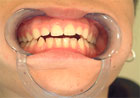

Fig.2 Ausencia de sectores posteriores

Este estudio, nos ayuda a mantener el concepto de que el aumento de la carga articular por pérdida del soporte posterior (ausencia de molares)

(Fig. 2), aumenta los signos y síntomas en los desórdenes craneomandibulares, incluyendo cambios estructurales óseos.